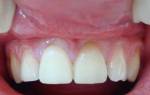

Для получения качественной цельнолитой коронки необходимо пройти несколько этапов производства. Сначала проводится осмотр и санация ротовой полости, а затем делается слепок зуба, который требует протезирования. Стоматологи используют безопасные слепочные массы из силикона, которые точно отображают анатомические особенности челюстного аппарата. Для комфорта пациентов и привыкания к протезам, им устанавливают временные коронки. Затем создается гипсовая модель будущего протеза, на основе которой изготавливают восковую заготовку, затем заменяемую на металлический сплав.

На втором этапе производится санация и подготовка ротовой полости для установки цельнолитых коронок. Зубы шлифуются, чтобы протезы плотно и точно прилегали. Затем протез одевается на зуб, а лишний воск удаляется через отверстия. Протез осматривается врачом и отправляется на доработку при необходимости.

На третьем этапе происходит примерка изделия, чтобы убедиться, что оно идеально подходит. Если есть неточности или несоответствия, коронка возвращается в лабораторию для доработки. После этого протез фиксируется при помощи специального цемента. Пациенты не должны испытывать неприятных ощущений и их жевательные функции не должны быть ограничены. Изготовление цельнолитой коронки может занять больше месяца, так как требуется внимательность и точность на всех этапах процесса.

image